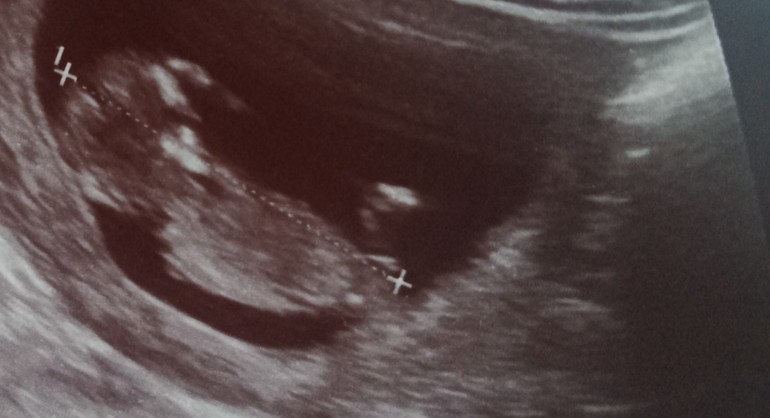

Ножка или половой бугорок?)

Пол малышаОчень уж интересно, кто у нас будет, сыночек или доченька) я уже несказанно счастлива 😍срок 12 недель 3 дня) знаю, что рано, но погадать хочется)

Как думаете, это бугорок или ножка?)

Может тут есть опытные мамы, которые умеют определять по фото узи)

Мне видится мальчик по последнему фото. Над крестиком небольшой такой вверх, у девочек он больше параллелен линии спины что ли.